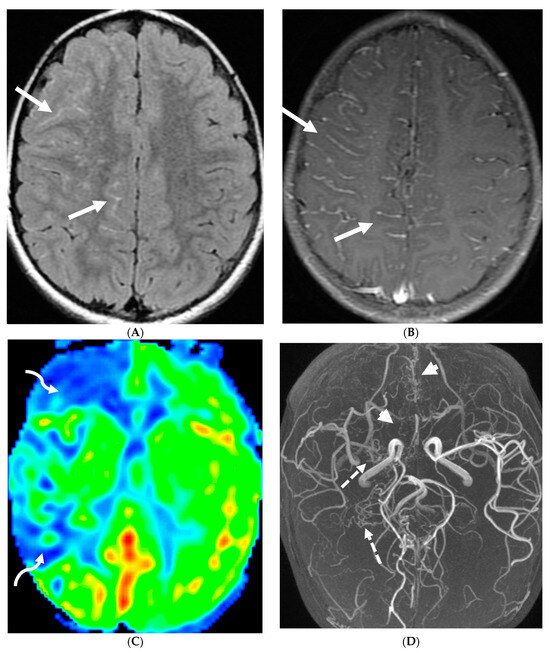

MRI, the standard noninvasive imaging modality, shows vascular narrowing on T2-weighted images and collateral vessels [91,92]. FLAIR sequence helps in detecting subtle areas of gliosis or chronic white matter ischemia. While DWI remains the optimal sequence for detecting acute ischemia, SWI helps in detecting acute or chronic microbleeds in addition to prominent deep medullary veins in areas with impaired blood flow (depicted as the “brush sign”). MR angiography defines the disease extent.

In children with moya moya, the LME is termed the “ivy sign” as the appearance resembles creeping ivy (Figure 18) [93]. LME arises due to two key factors in MMD, namely neovascularization and retrograde flow from congested pial vessels [94].

Figure 18.

Axial FLAIR (A), MRA (B), axial ASL perfusion (C) and axial T1 post contrast (D): 7-year-old girl with Down’s syndrome: Abnormal FLAIR hyperintense signal with LME along the right cerebral convexity sulci, predominantly in the frontoparietal region representing “ivy sign” (arrows). Asymmetric decreased perfusion in the right frontal and temporal regions (curved arrows). The M1 segment of right MCA is not visualized with extensive moyamoya vessels (dashed arrows). The M2 and M3 branches of right MCA are asymmetrically attenuated. Bilateral A1 segments are not identified with extensive collateralization and diminutive caliber of A2 and A3 segments (arrow heads).

Although LME is a supportive feature in the diagnosis of moya moya, LME is a marker of collateral vessel status and less LME is a marker of severe clinical symptoms and poor postoperative outcomes [95]. In addition, degree of reduction of LME after surgery has been proposed to be a marker of effective surgery [96].